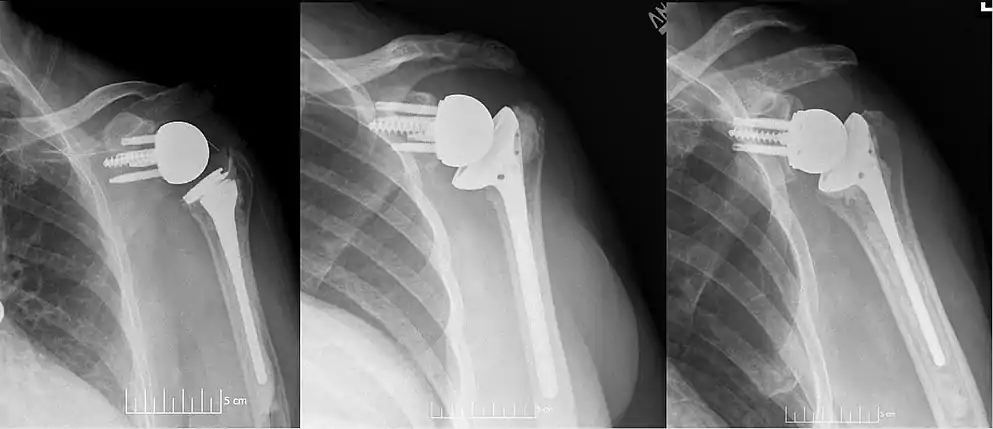

![]() Plain film radiograph in anteroposterior (AP) view of a right shoulder status post reverse shoulder arthroplasty using a prosthesis with a lateralized center of rotation. | |